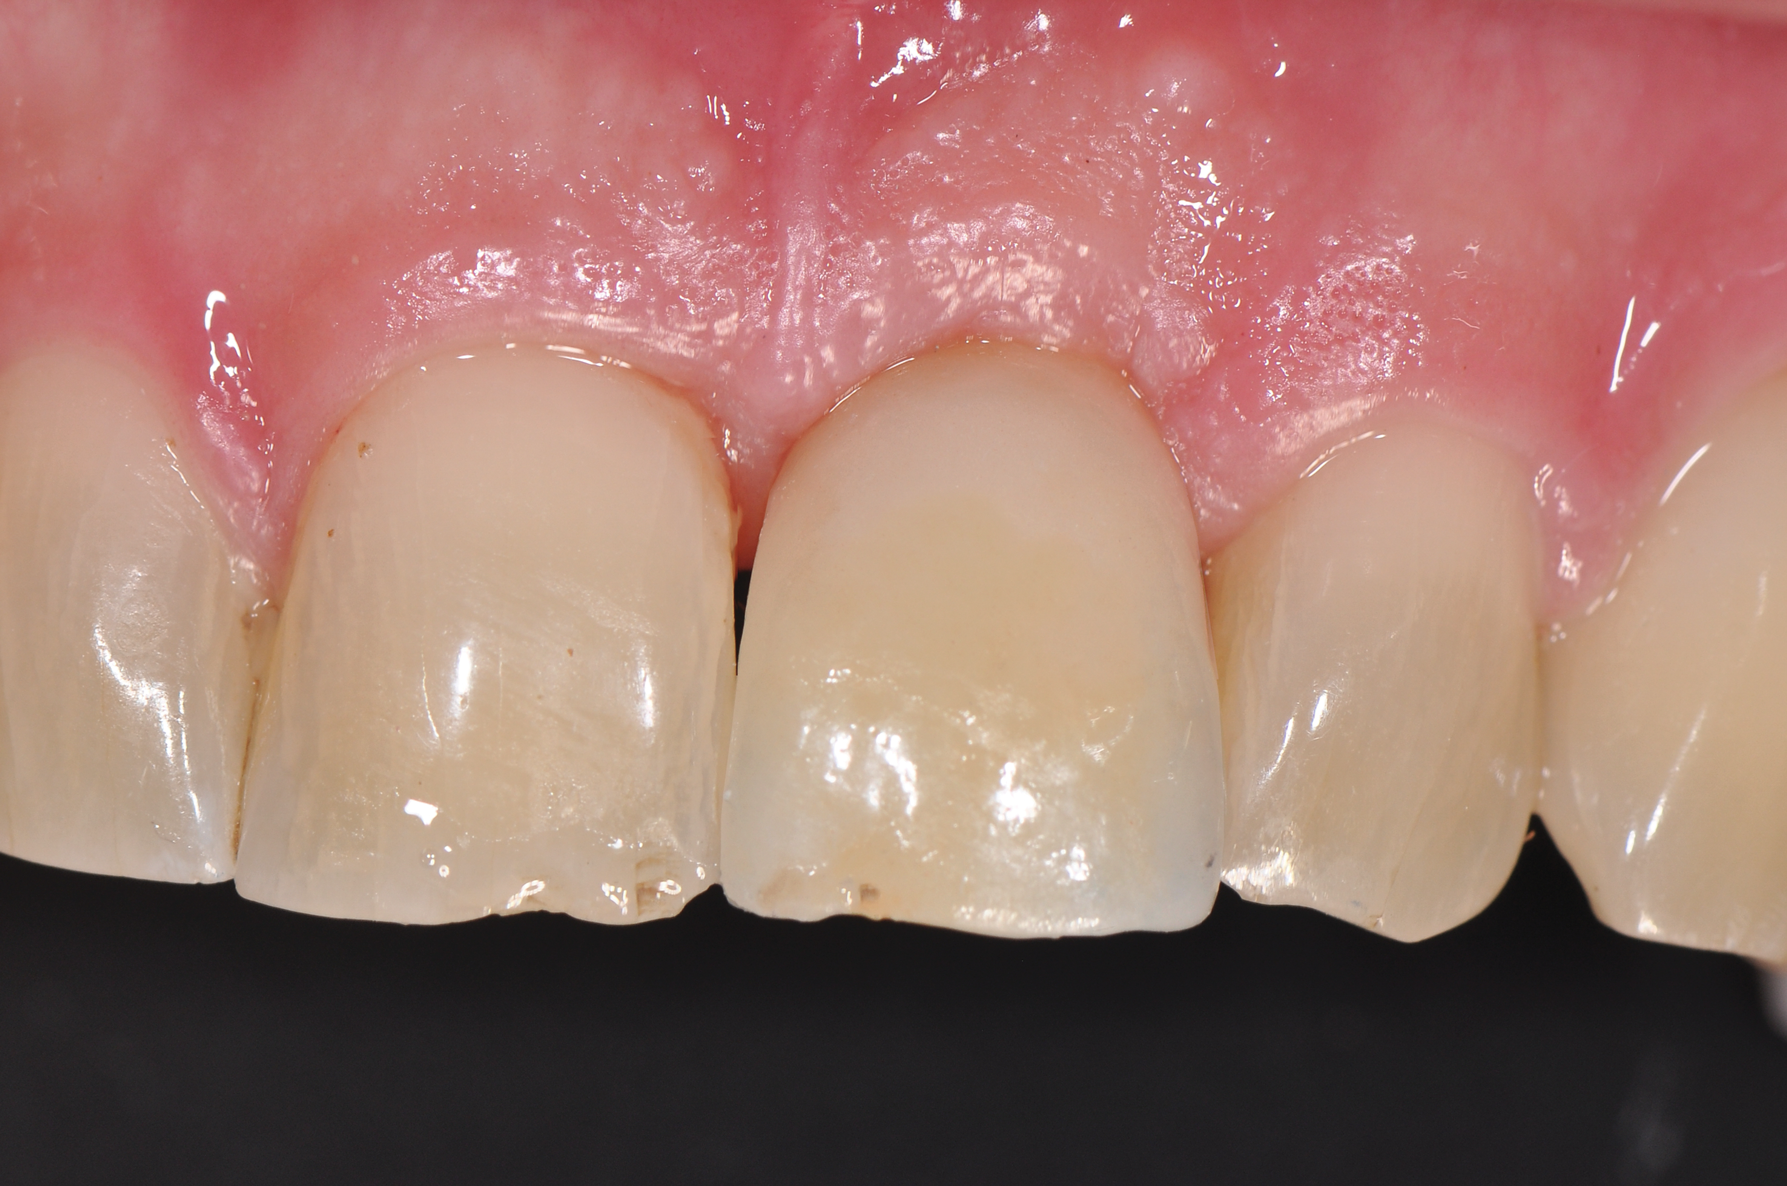

Still, as with titanium implants, undesirable recession with an exposed implant shoulder may occur in rare cases with ceramic implants. Nonetheless, from an esthetic point of view, this inflammation-free recession of the gingiva is likely to be tolerated much better by patients concerned with the dark margins of titanium implants (Figure 2).

Fig 2. Recessions in ceramic (left) and titanium (right) implants.

Figure 2